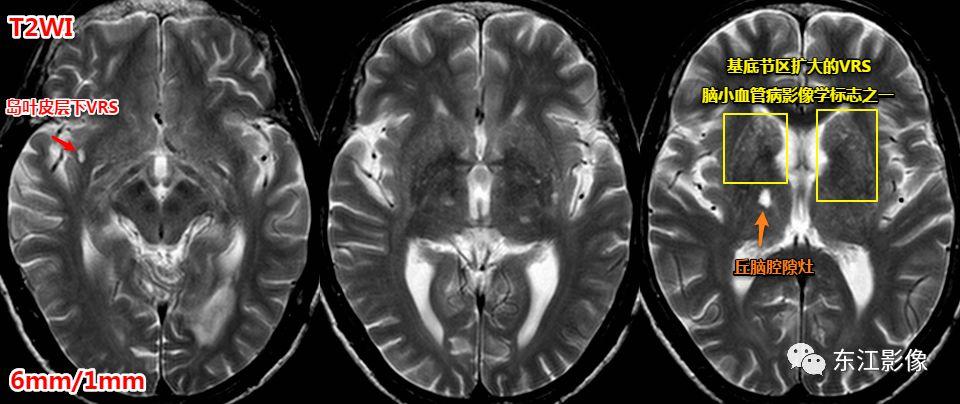

1. 扩大的血管周围间隙

扩大的血管周围间隙非常常见。

- 常见部位:前穿质区,外囊区,额顶叶皮层下,中脑。——务必熟记!

- 其他部位:丘脑,颞枕叶皮层下,侧脑室周围白质,小脑。

注意,扩大的血管周围间隙也是脑小血管病的影像学标志之一,但并非所有扩大的血管周围间隙均与脑小血管病有联系。

一般认为,基底节区中上区域扩大的血管周围间隙多与脑小血管病有关系。

基底节区扩大的血管周围间隙,丘脑腔隙灶典型影像,均为脑小血管病影像学标志。